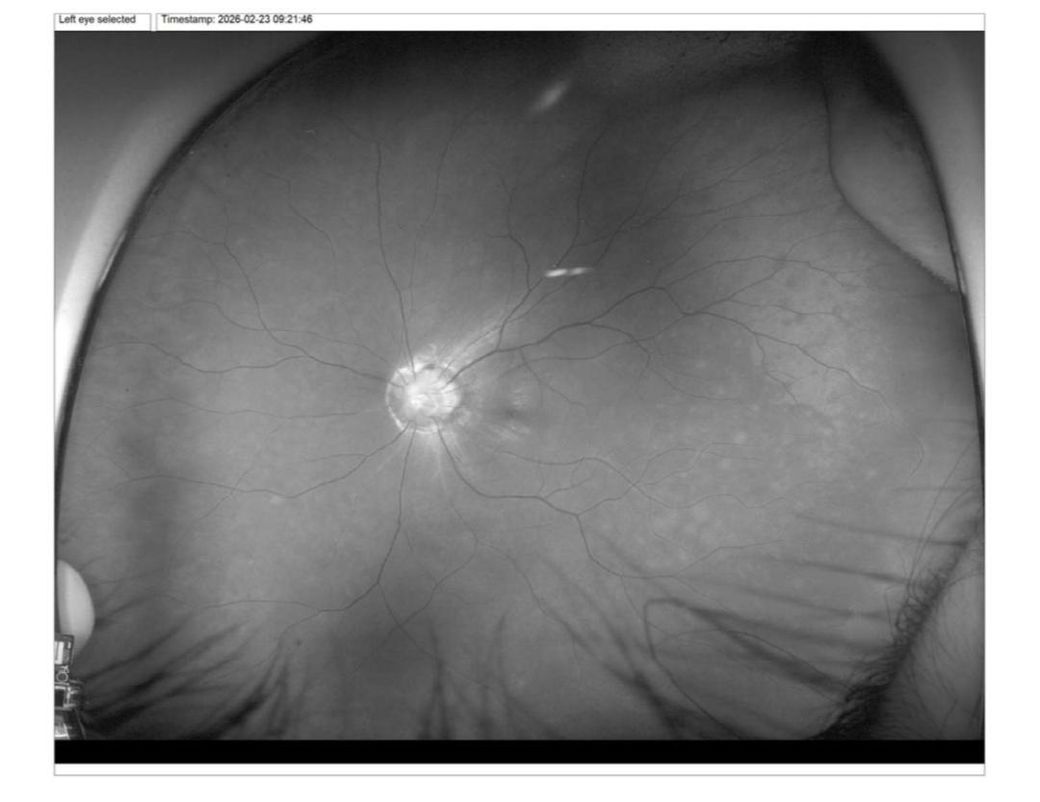

왼쪽눈엔 원래 나팔꽃 증후군이 있었고 1월 중반쯤에 왼쪽눈에 중심암점이랑 소시증이랑 어둡고 흐리게보이는 증상을 발견했고 여러 검사를 받았는데 진단결과가 예상했던 중심성 망막염이 아닌 시력저하라 중심성망막염이 아니라면 이유랑 다른 병인지좀 알고싶습니다. 지금은 소시증, 어둡고 흐리게 보이는건 그대론데 암점은 조금 줄어들었습니다

올려주신 사진들을 보니 망막 중심부 아래에 물이 조금 고여 있는 상태네요.

이런 소견은 전형적인 중심성 망막염으로 보여 걱정이 참 크셨을 것 같아요.

다행히 이 질환은 스트레스를 피하고 푹 쉬면 자연히 회복되는 경우가 많습니다.

다만 시력이 변하거나 휘어 보일 수 있으니 정기적으로 꼭 확인해 보세요.